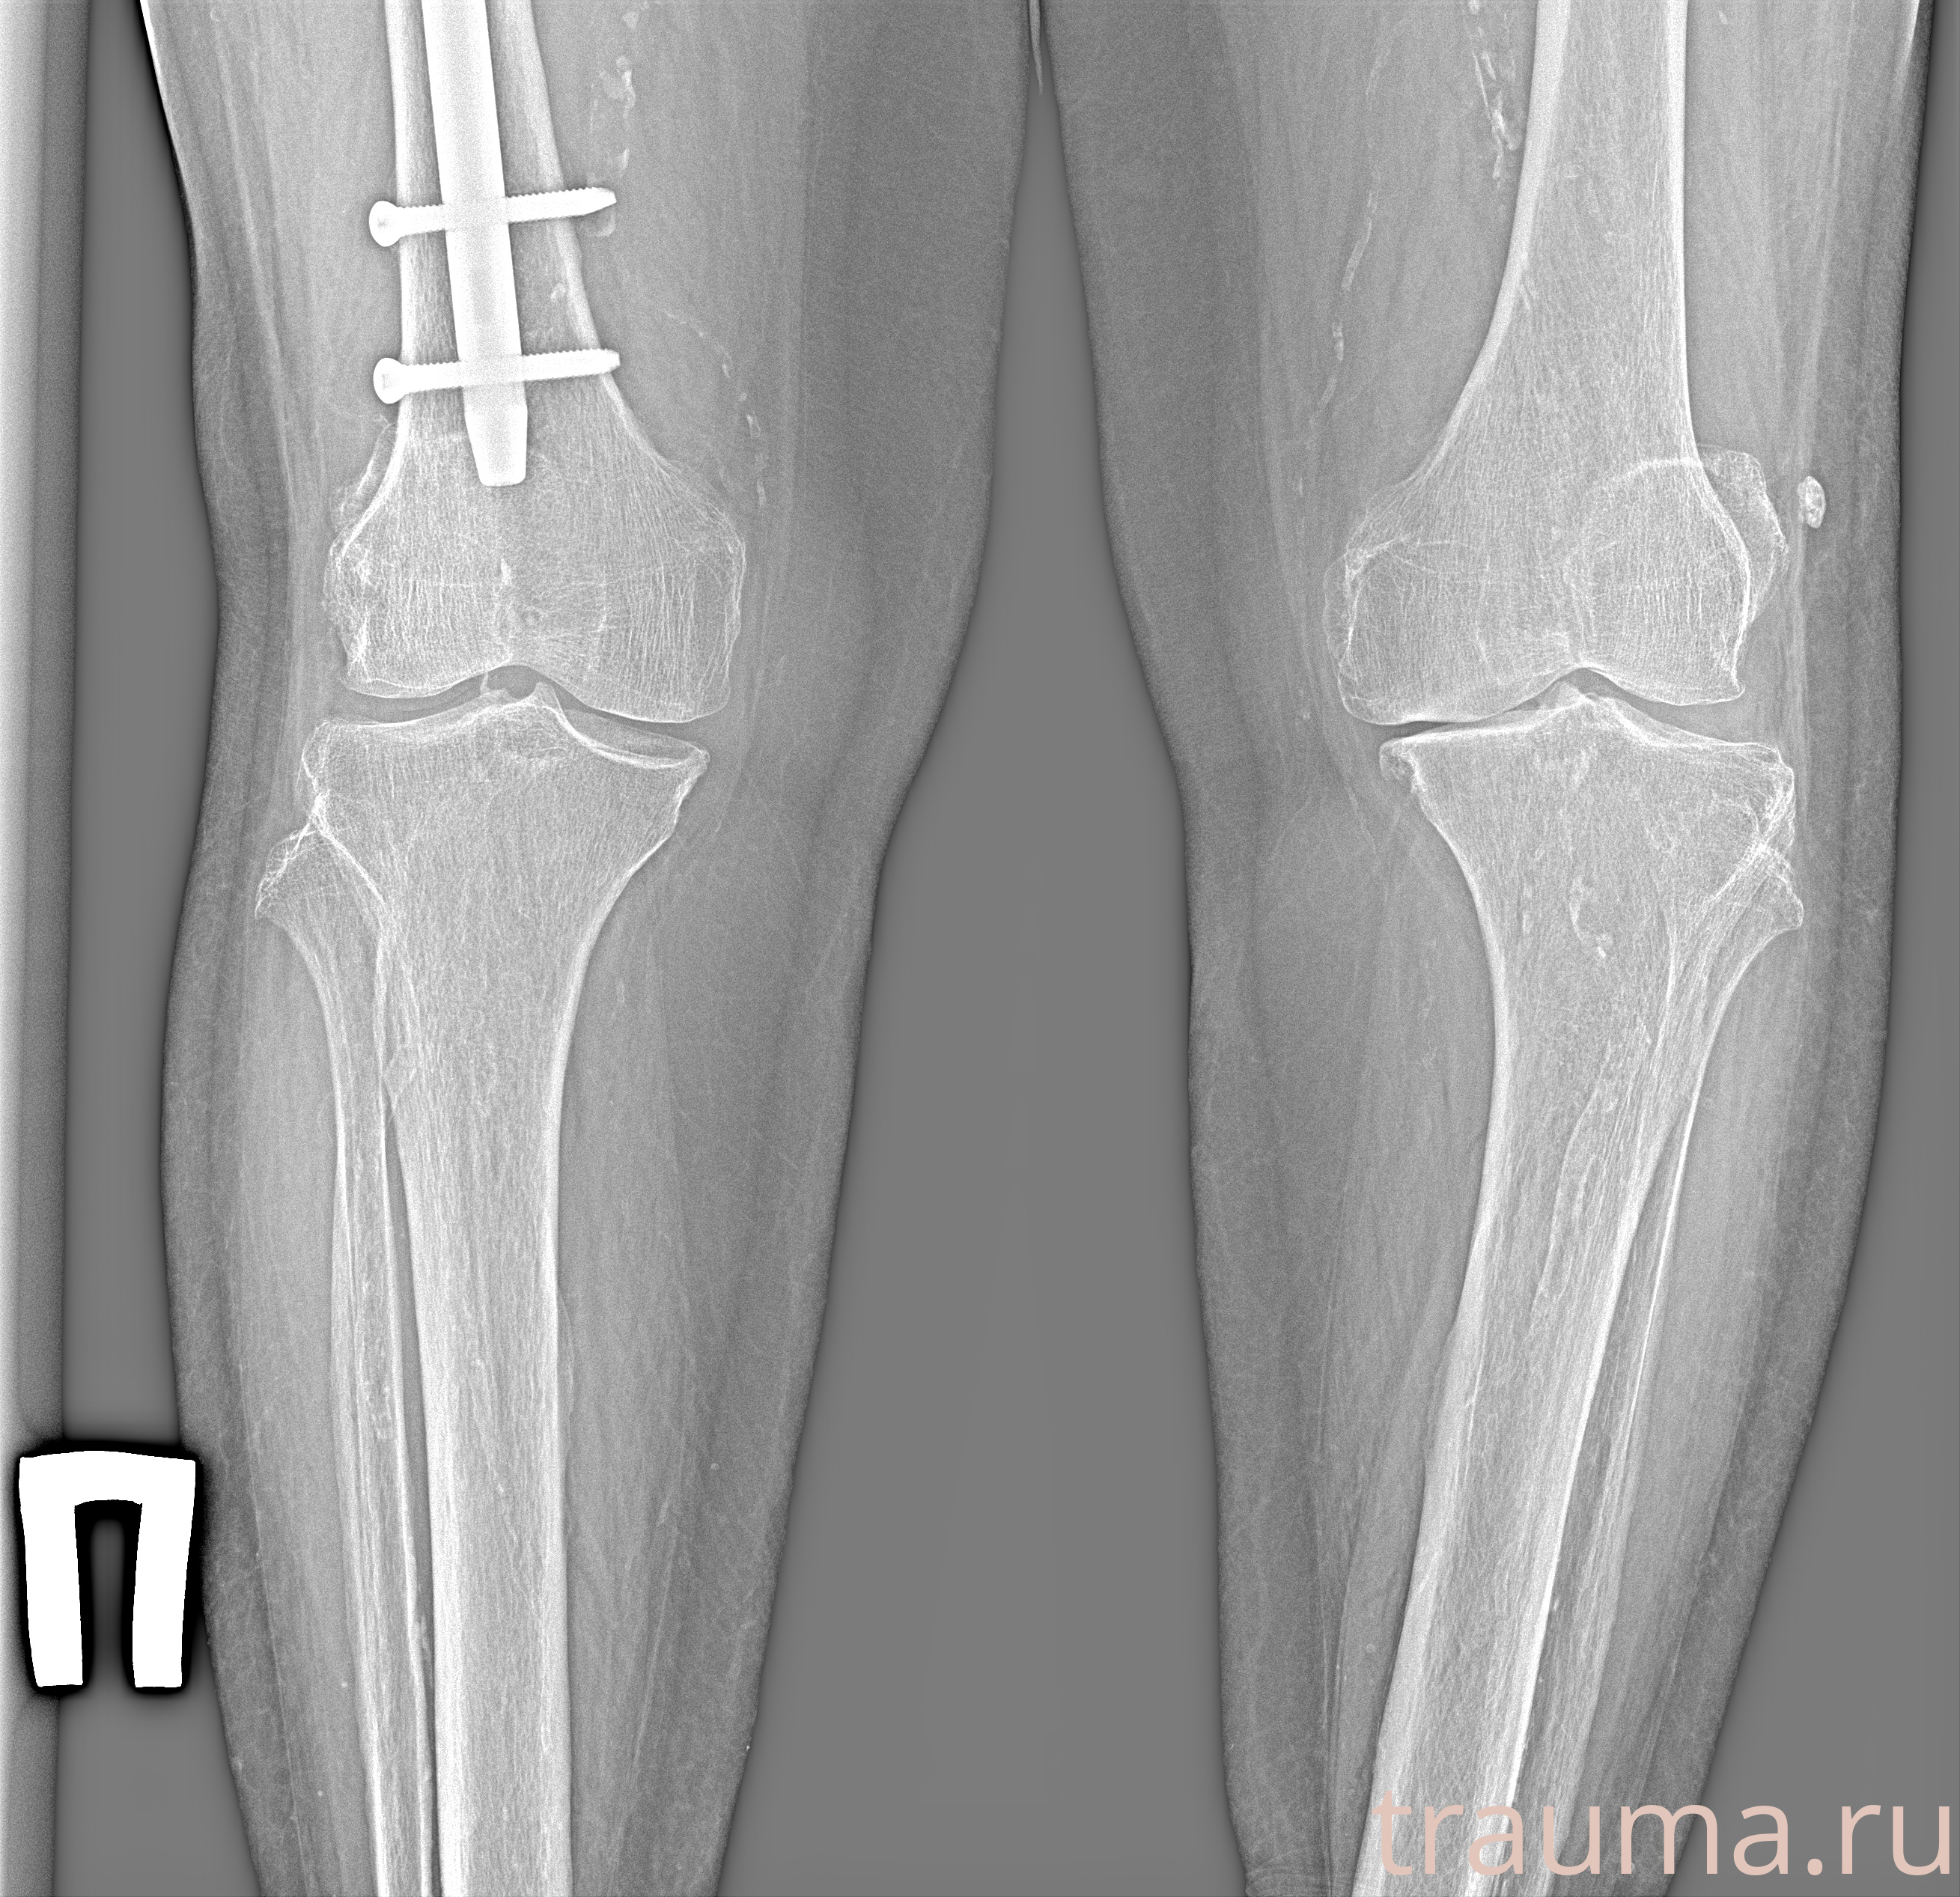

Рентгенограммы